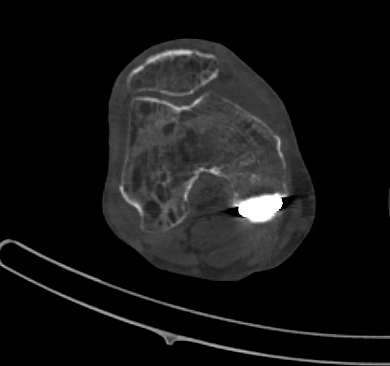

L’imagerie vient renforcer le diagnostic : la scintigraphie osseuse montre classiquement une hyperfixation dans la phase osseuse, tandis que l’IRM peut révéler un œdème médullaire, une déminéralisation mouchetée et des signes inflammatoires périarticulaires. Ces examens permettent de confirmer le diagnostic en cas de doute clinique ou d’évolution atypique.